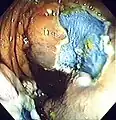

An advantage of colonoscopy over X-ray imaging or other less invasive tests is the ability to perform therapeutic interventions during the test. A polyp is a growth of excess of tissue that can develop into cancer. If a polyp is found, for example, it can be removed by one of several techniques. A snare device can be placed around a polyp for removal. Even if the polyp is flat on the surface it can often be removed. For example, the following shows a polyp removed in stages:

-

Polyp is identified. -

A sterile solution is injected under the polyp to lift it away from deeper tissues. -

A portion of the polyp is now removed. -

The polyp is fully removed.